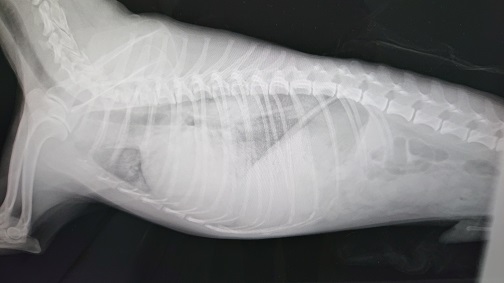

犬の心臓病 僧帽弁閉鎖不全症

特に小型犬などに多く見られ、ワンちゃんの心臓病としてもっともポピュラーと言えるのが心臓弁膜疾患です。中でも左心房と左心室を分ける僧帽弁という弁膜に異常をきたし、血流が悪くなる結果様々な全身症状を示すようになります。(=僧帽弁閉鎖不全症)

心臓弁が機能しなくなり血液が逆流すると、全身からの血流や肺への血流が滞り(=うっ血)心房や心室に負荷がかかり心拡大へと進行します。

検査を受け、病期(ステージ)を診断してどのような投薬が必要かを判断します。アメリカ獣医内科学会(ACVIM)が提唱する進行のステージA→B1→B2→C→Dのうち、ステージB2以上が治療開始の対象となります。レントゲン検査および超音波検査でこれらステージを確認します。